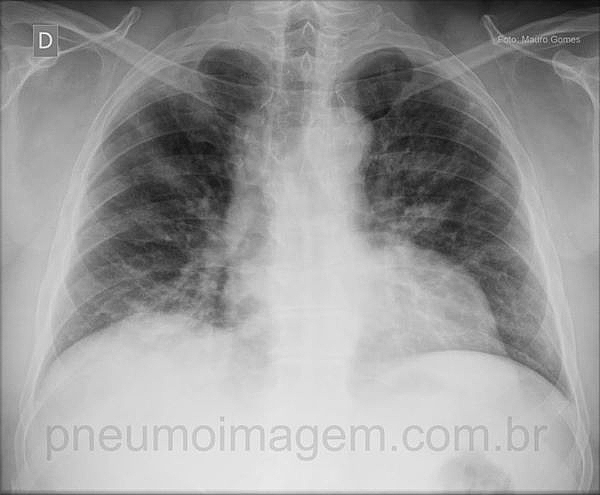

CASO CLÍNICO #21Paciente do sexo masculino, 48 anos de idade, obeso, com quadro de dispneia, tosse e febre acompanhando episódio gripal. Nega tabagismo. Em 48h houve evolução para insuficiência respiratória. Observe a radiografia do caso, exercite seu raciocínio diagnóstico e deixe seus comentários abaixo.

Male patient, 48 years old, obese, with dyspnea, cough and fever during flu episode. Denies smoking. In 48 hours there was progress to respiratory failure. Note the radiograph of the case, exercise their diagnostic reasoning and leave your comments below.